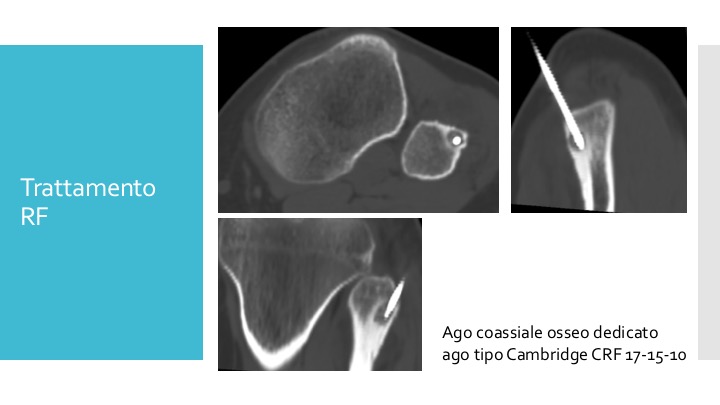

La termoablazione è una tecnica mini-invasiva guidata dai raggi X. Consiste nell’inserire un ago sottile nel nodulo osseo e, attraverso l’ago, viene erogata energia termica (calore) per “bruciare” le cellule tumorali.

- Guida per immagini: il radiologo utilizza raggi X (fluoroscopia o TAC) per guidare l’ago con precisione fino all’osteoma osteoide.

- Posizionamento dell’ago: l’ago viene inserito attraverso la pelle e posizionato esattamente al centro del nodulo osseo.

- Ablazione termica: attraverso l’ago viene erogata energia termica che distrugge le cellule tumorali.